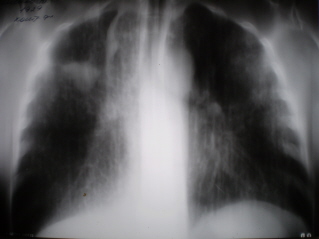

Протокол. Илл. № 1. На обзорной цифровой флюорограмме, произведенной в прямой стандартной проекции определяется синдром двусторонней довольно мономорфной диссеминации. Очаговые тени преобладают в средних и нижних отделах легочных полей. В верхних отделах количество очаговых теней меньше. Тень левого корня не дифференцируется, гомогенизирована. Справа в верхнем легочном поле каплевидная тень непарной вены.